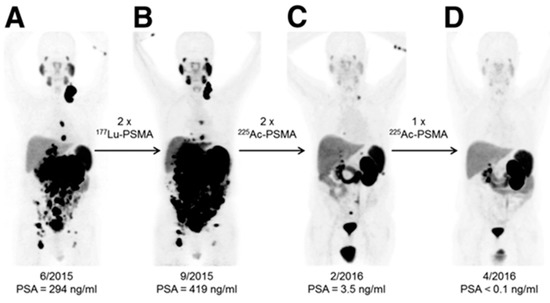

Alpha (α)-particles have a linear energy transfer of 100 keV/µm compared to the 0.2 keV/µm of β-particles in tissue. The higher LET means a larger portion of the total radiation dose is delivered over an equal pathlength. Alpha (α)-particles can deliver up to 1000× more dose to cells than β-particles, even with the same number of radioactive decays. This high energy allows for double rather than single-strand DNA breaks, leading to increased cell death. Cancer cells can adapt to single-stranded DNA breaks and survive, but struggle when double-strand breaks occur. An incredible example of this occurred when β-resistance was overcome with α-particle therapy with Ac-225-PSMA [49]. As shown in Figure 5, Lu-177-PSMA was unable to debulk tumors or decrease PSA levels in this patient, but repeated doses of Ac-225-PSMA led to complete tumor eradication and a return to normal levels of PSA. Improvements in neuroendocrine cancer therapy are also seen when an α-particle emitter is used instead of β-radiation [50,51].

Figure 5.

Alpha (α)-particle therapy overcomes β-resistant cancer. This imaging was performed using Ga-68-PSMA-11 PET/CT scanning. Kratochwil, C. et al. [49] reports, “In comparison to initial tumor spread (A), restaging after 2 cycles of β-emitting 177Lu-PSMA-617 presented progression (B). In contrast, restaging after second (C) and third (D) cycles of α-emitting 225Ac-PSMA-617 presented impressive response.” This research was originally published in The Journal of Nuclear Medicine [49].